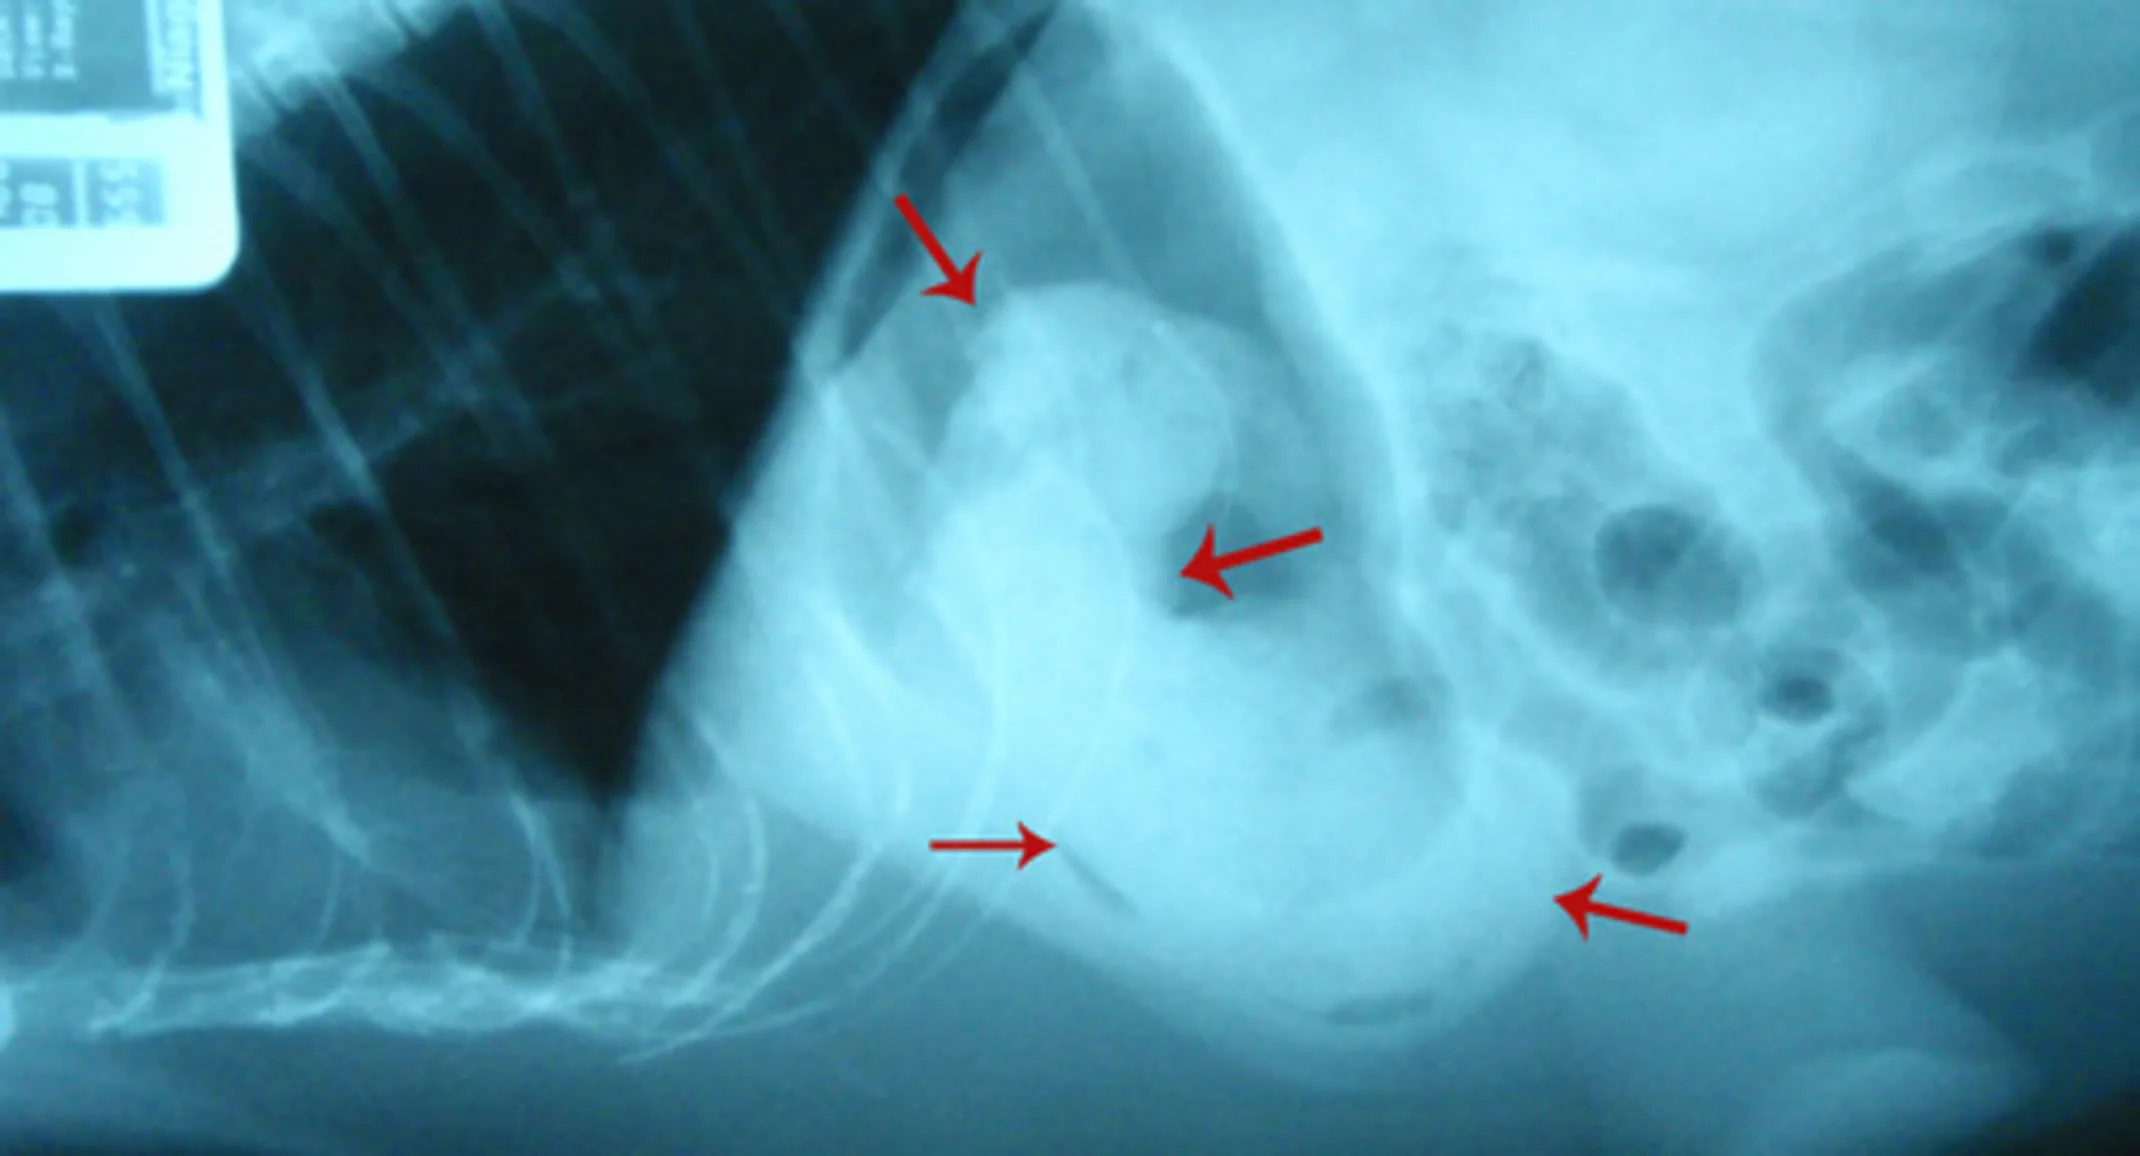

Murphy is a 10 year old male Himalayan cat who presented to us with a history of not eating for a few days. He was also vomiting and the owners noticed blood in the vomit at times. Murphy was admitted for bloodwork and abdominal radiographs (x-rays) to try and track down the cause of his illness. The blood results were normal, however the x-rays revealed an object lodged in his stomach.

The blood results were normal, however the x-rays revealed an object lodged in his stomach. Lateral abdominal radiograph view with Murphy lying on his side showing an object in the stomach (outlined by the red arrows). The heart, lungs, and chest are seen to the left and the rest of the abdomen.